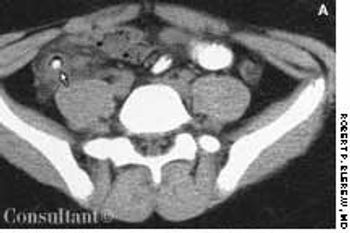

A 15-year-old boy presented with sharp, right lower quadrant abdominal pain, nausea, vomiting, and fever of 2 days' duration. His white blood cell count was 15,000/mL with a shift to the left on the differential. Right lower quadrant rebound tenderness was noted.

The diagnosis of acute appendicitis is usually straightforward. When the presenting symptoms are atypical, abdominal ultrasonography can be of diagnostic assistance if it shows the thickened walls of the appendix and a distended, noncompressible lumen.